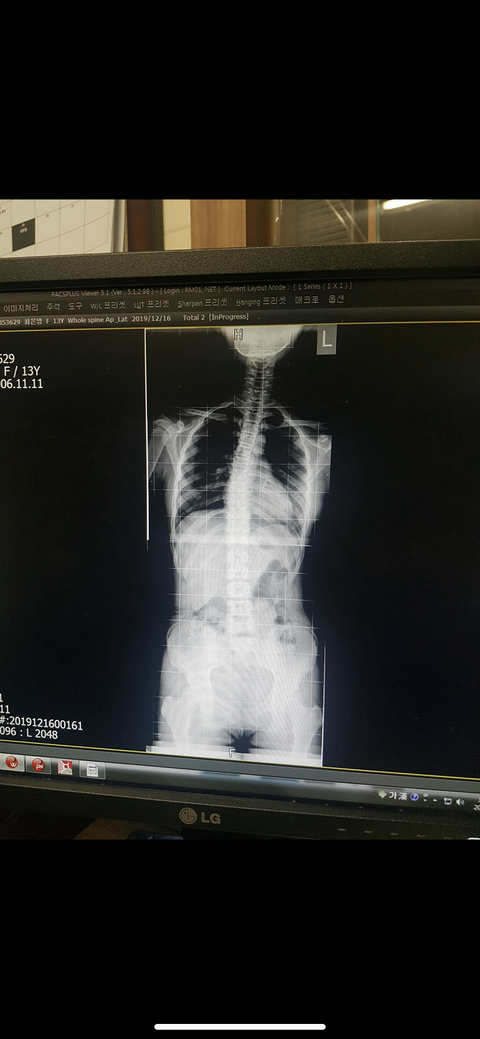

[꼭조언부탁]

척추측만증 이정도면 휜 각도가 몇도쯤 될까??